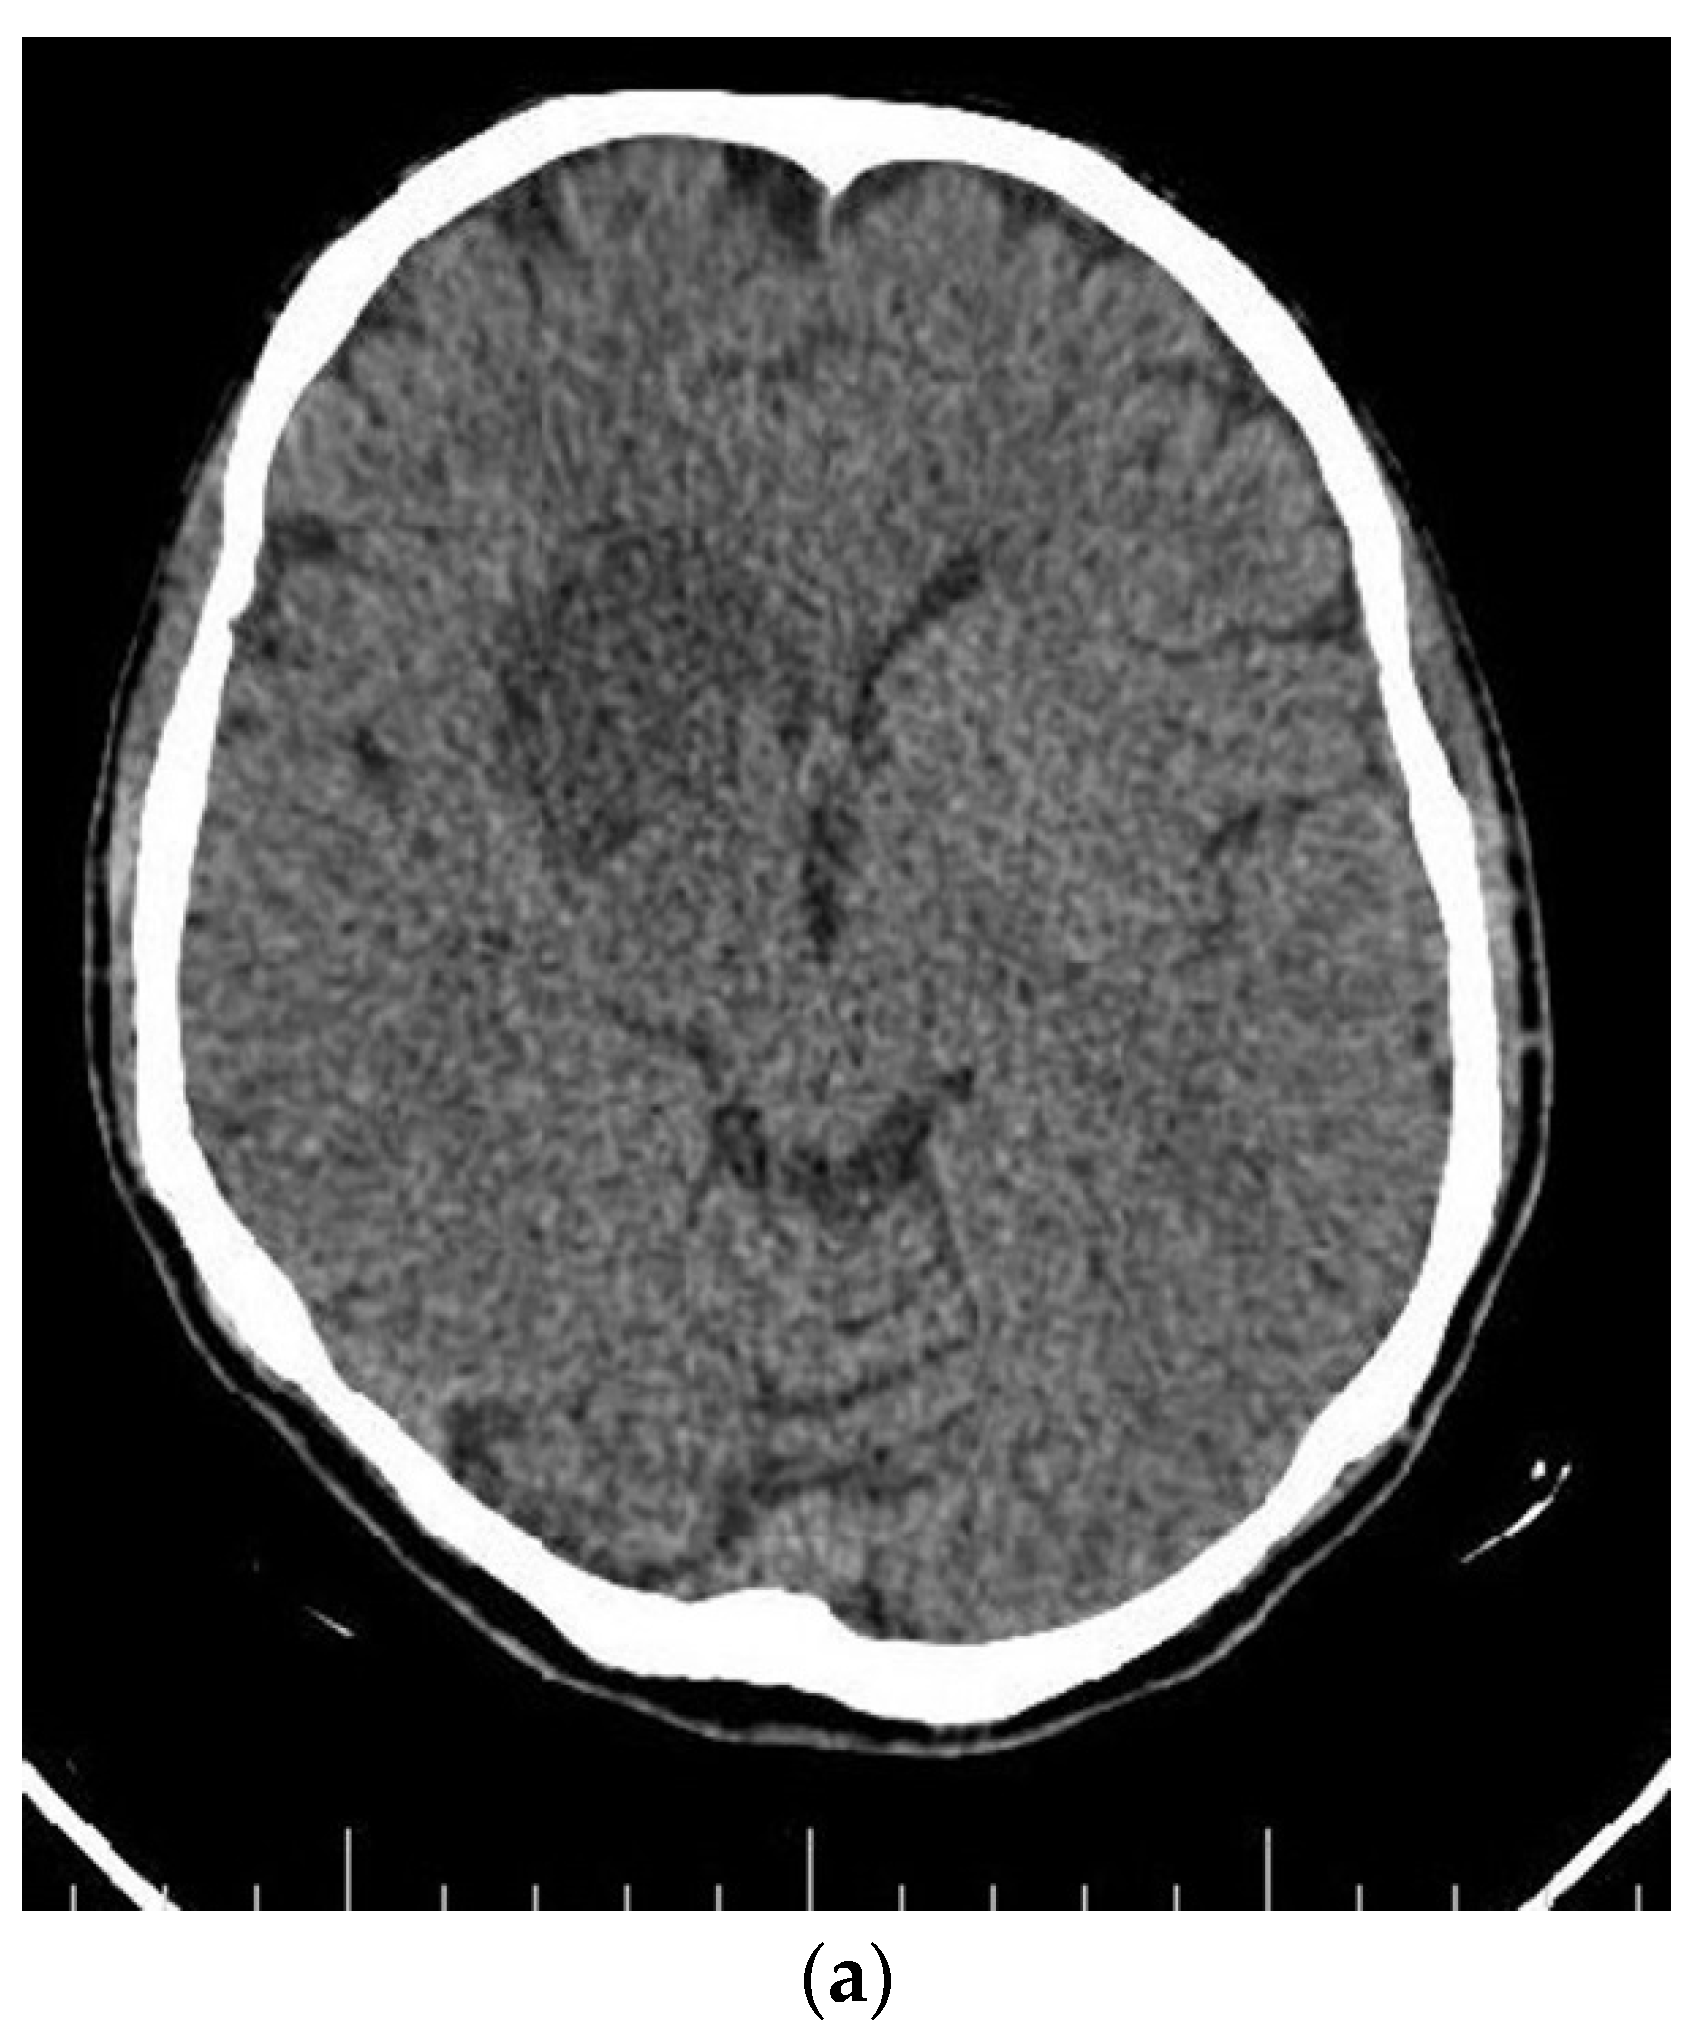

| The current case | 29, female | C2 | CD45, CD43, CD68, S100 | Surgery and radiotherapy | Brain metastasis after 9 months |